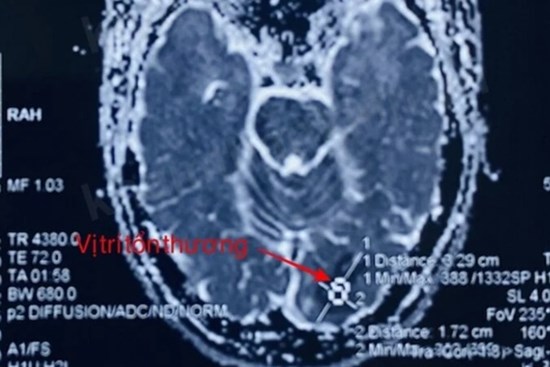

Người phụ nữ bị cùng lúc 2 dạng đột quỵ đặc biệt nguy hiểm

Nhập viện với chẩn đoán bị nhồi máu não bán cầu trái, yếu liệt nửa người. Qua kiểm tra hình ảnh, bác sĩ phát hiện ngoài tình trạng bị nhồi máu não, bệnh nhân còn có nguy cơ vỡ túi phình dẫn đến xuất huyết não.